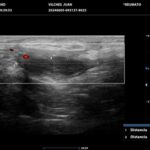

La HS es una enfermedad crónica, inflamatoria inmunomediada, sistémica, recurrente y debilitante de los folículos pilosos terminales con origen en las glándulas apocrinas de estos. Presenta habitualmente lesiones dolorosas, profundas e inflamadas, localizadas más frecuentemente en las regiones axilares, inguinales y anogenitales. El 80% de las lesiones tienen ubicación profunda de difícil acceso al examen físico. Su diagnóstico es clínico pero el ultrasonido (US) de alta resolución con Doppler es un método que cumple actualmente un rol esencial para establecer el diagnóstico, estadificar la enfermedad y detectar actividad, incluso en el caso de lesiones no pesquisadas en el examen físico. También nos permite monitorear el estado y la progresión de la HS, facilitando la evaluación rápida de distintos enfoques terapéuticos. Incluso, los cambios ecográficos pueden modificar la conducta terapéutica.

Hallazgos imagenológicos

Los hallazgos ecográficos más relevantes son el ensanchamiento de folículos pilosos, engrosamiento y ecogenicidad anormal de la dermis, nódulos pseudoquísticos dérmicos, colecciones líquidas y tractos fistulosos. Por otro lado, el US nos permite valorar la localización exacta y extensión de las lesiones, su ecogenicidad, el grado de vascularización al examen Doppler y las eventuales complicaciones, e incluso la modificación de las lesiones en respuesta a la terapéutica instaurada. La HS se estadifica clínicamente mediante la clasificación de Hurley y los hallazgos ecográficos muestran correlación con cada estadio clínico.

El diagnóstico ecográfico resulta de importancia diagnóstica, tal es así que la ecografía de alta resolución y el estudio Doppler han ocupado un lugar preponderante en los últimos años. La ecografía de la piel permite identificar lesiones no encontradas en el examen físico, evaluando de manera fehaciente su extensión anatómica. El empleo de la ecografía en la HS es ideal, ya que el 80% de las lesiones ocurren en las capas más profundas y no en la superficie de la piel. Permite evaluar la localización exacta y extensión de las lesiones, su ecogenicidad, el grado de vascularización al examen Doppler, las eventuales complicaciones, e incluso la respuesta terapéutica.

El estudio ecográfico de alta resolución con Doppler tiene un rol fundamental en la categorización de las lesiones de HS en profundidad, incluso las subclínicas. Debemos incluir al US como técnica de elección para estadificar y monitorear pacientes con HS, ya que nos permite acceder a un diagnóstico rápido de lesiones típicas con las que podremos, en conjunto con la clínica, estadificar y seguir en el tiempo a los pacientes.